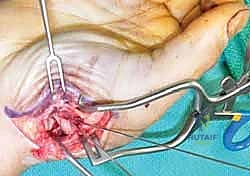

2. الرد المفتوح والتثبيت الداخلي (ORIF - Open Reduction and Internal Fixation)

عندما يكون الكسر مفتتًا (مثل كسر رولاندو) أو لا يمكن رده بشكل مغلق، يتم اللجوء إلى الجراحة المفتوحة.

* الخطوات: يقوم الجراح بعمل شق جراحي دقيق (غالباً بشق Wagner) فوق قاعدة الإبهام للوصول المباشر إلى المفصل.

* يتم تجميع الشظايا العظمية بدقة متناهية تحت التكبير الجراحي (Microsurgery).

* يتم تثبيت العظام باستخدام شرائح تيتانيوم صغيرة جداً (Mini-plates) ومسامير دقيقة (Screws).

* الميزة: يوفر تثبيتاً صلباً جداً (Rigid Fixation) يسمح ببدء العلاج الطبيعي وحركة المفصل في وقت مبكر جداً، مما يقلل من التيبس.